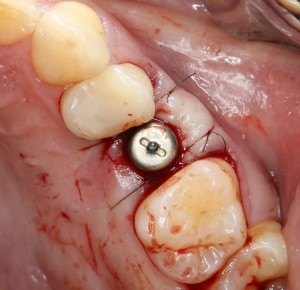

Ничего не стоит поставить имплантат в такие объемы кости и при таком качестве слизистой оболочки:

Обратите внимание: даже там, где отсутствовала вестибулярная стенка лунки, восстановилась костная ткань:

Теперь мы просто ставим имплантат. Без синуслифтинга. И без проблем со стабилизацией:

А качество и объем слизистой оболочки настолько хороши, что можно сразу поставить формирователь десны:

и через 3 месяца приступить к протезированию:

Итого: 4,5 месяца, удаление-аугментация лунки плюс имплантация-формирование десны. Всего две операции. И никаких проблем.